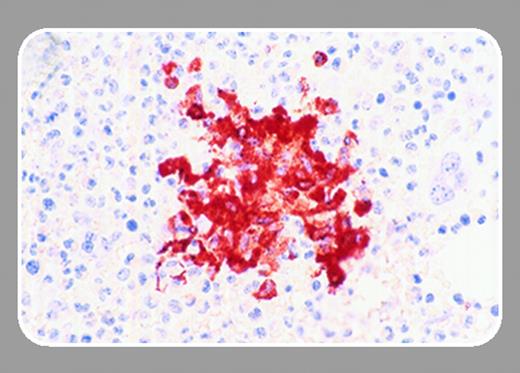

Known to be associated with altered c-kit, systemic mastocytosis (SMCD) was an additional hematologic disorder explored for potential imatinib sensitivity; however, an association with the imatinib-insensitive Asp816Val enzymatic site c-kit mutation made benefit seem less likely.4 Pardanani and colleagues nonetheless recently reported activity of imatinib in a subset of SMCD patients,5 and, in this issue of Blood (page 3093), add another chapter to the story by further defining a subgroup of SMCD patients with eosinophilia (SMCD-eos) harboring a FIP1L1-PDGFRA fusion tyrosine kinase. Loss of fluorescence in situ hybridization of a probe developed against the deleted region on 4q12, cysteine-rich hydrophobic domain 2 (CHIC2), provided surrogate identification of FIP1L1-PDGFRA fusion, and was found in imatinib-sensitive SMCD-eos patients. In one patient, FIP1L1-PDGFRA fusion was confirmed with polymerase chain reaction performed on eosinophil and neutrophil populations. Although common to both HES and SMCD-eos, eosinophilia did not necessarily predict deletion at CHIC2, consistent with this group's prior demonstration of potential for response to imatinib in SMCD without eosinophilia.FIG1